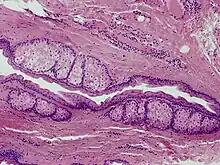

Steatocystoma multiplex, is a benign, autosomal dominant congenital condition resulting in multiple cysts on a person's body. Steatocystoma simplex is the solitary counterpart to steatocystoma multiplex.[2]

The cysts are mostly small (2–20 mm) but they may be several centimetres in diameter. They tend to be soft to firm semi-translucent bumps, and contain an oily, yellow liquid. Sometimes a small central punctum can be identified and they may contain one or more hairs (eruptive vellus hair cysts). They may become inflamed and heal with scarring, like acne nodules (see nodulocystic acne and hidradenitis suppurativa).

Steatocystomas are thought to come from an abnormal lining of the passageway to the oil glands (sebaceous duct).